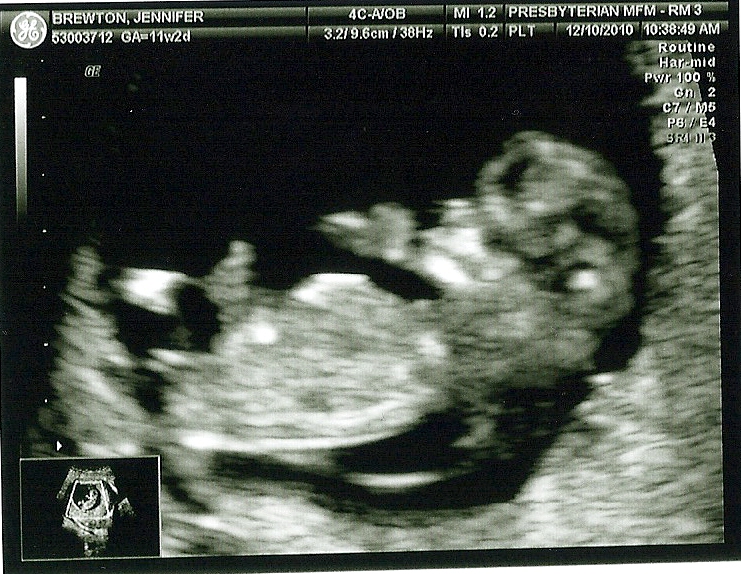

On December 10th, Dan and I went down to the city to have another ultrasound done, and I was a ball of nerves once again. At this point I was 11 weeks 2 days and I was excited to see the baby, but worried that the same thing that happened during my last pregnancy may happen again. I was feeling a little more symptomatic this pregnancy, I was very hungry and having a bit of nausea. I felt like I was always tired and I had had a bit of a stretching feeling in my lower abdoman (which they say are your ligamants stretching to accomodate your growing uterus) so I felt like everything was going well, but I just didn’t know, and I was getting anxiety which was not healthy for me or for the baby. Dan, once again, was my rock, and assured me time and again that I was fine and always reminded me to think positively. I don’t know what I would do without him, and I am grateful every day for him and his optimistic outlook on life. He sat next to me in the ultrasound room, held my hand and made light of everything so I would calm down and relax. As soon as the wand was on my belly and I saw the image of our baby it was like a huge weight was lifted off of my chest, and I could breath again. It was much bigger than last time, and actually looked like a baby and we were immediately able to see the flicker of the heart and hear it beating 168 bpm, fast and strong. We promised our Mom’s that we would text them as soon as we had any news so Dan was on that right away, and everyone was happy!

It was amazing to see the head and the body, and the arms and legs moving all over the place (Definitely its’ fathers child, can’t sit still ) Everytime the ultrasound tech would try to take a picture the baby would make a jerky movement and kind of blur the image so we got a lot of pictures. The Dr. came in checked me again and the baby had flipped to the other side! It was the neatest thing!! He also confirmed that everything looked great and that the baby was developing exactly as it should be.